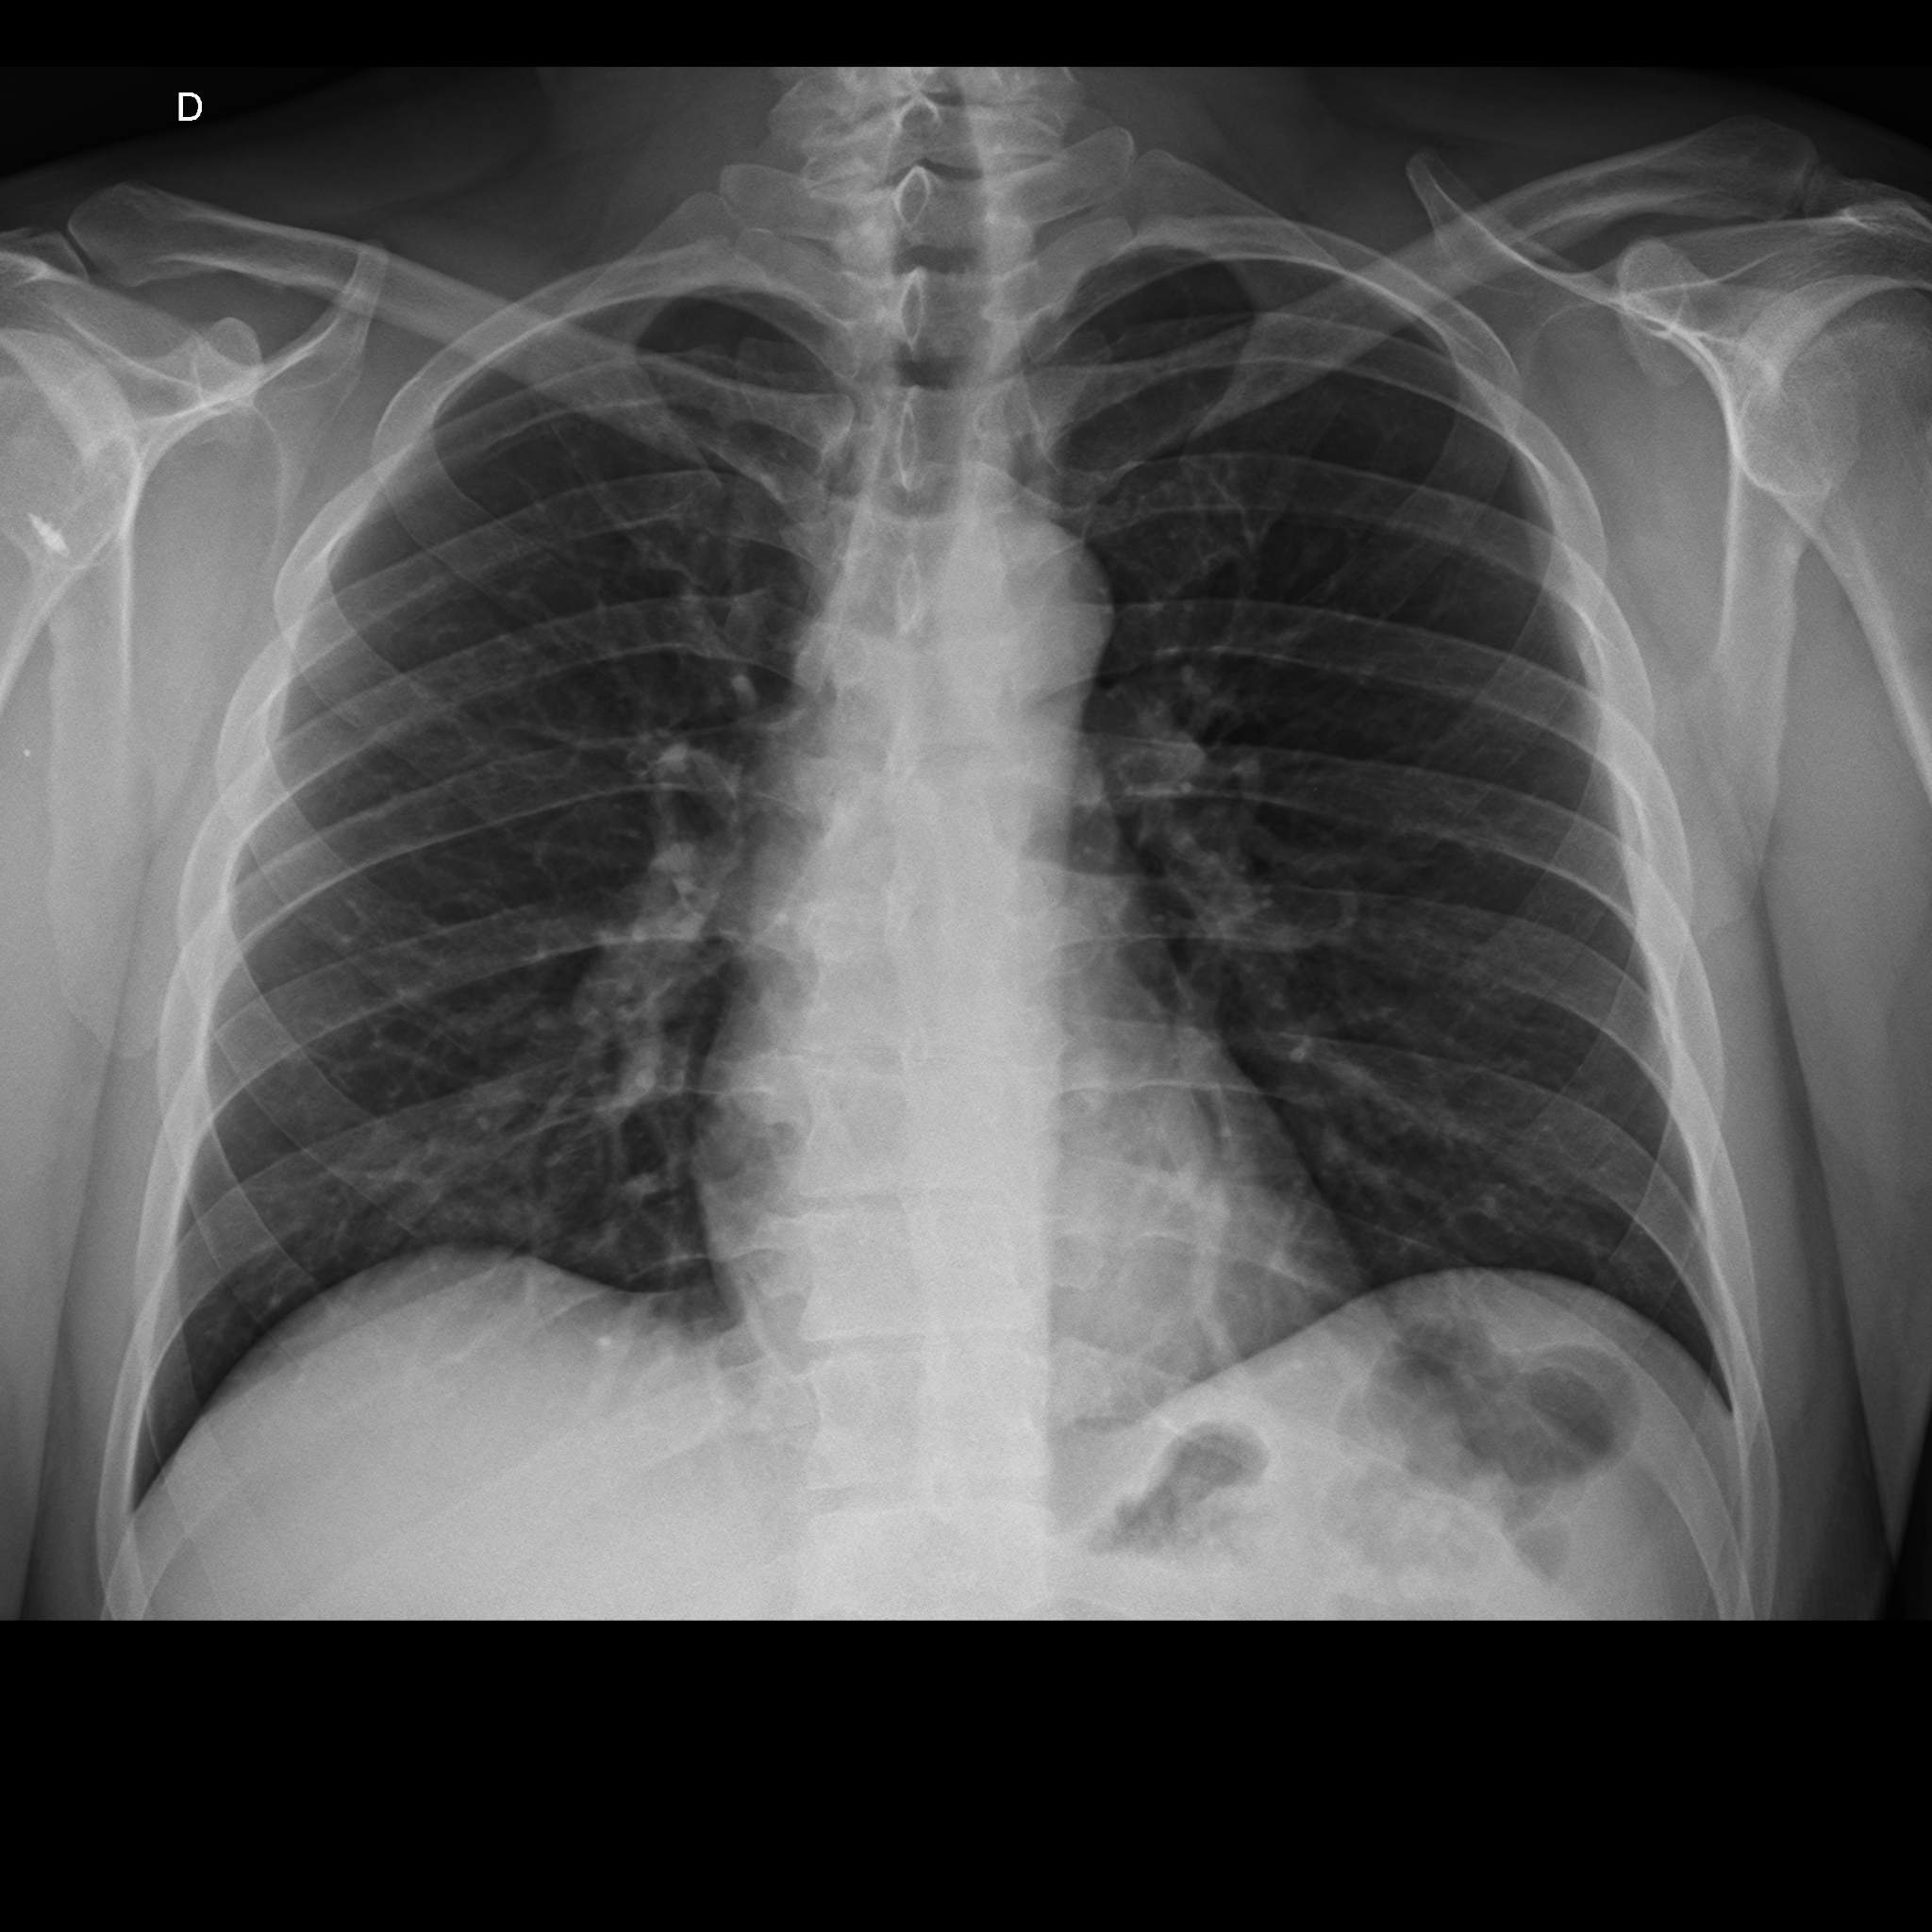

Demanda: Estudo de Caso Clínico (qual o meio de obte-lo: contrato NDA, orçamento?) das análises que fizemos (em anexo) de raio x e tomografia computadorizada obtidos em base pública realizado sob plataforma pública de deep learning com modelo abastecido por datasets públicos de pacientes suspeitos de contágio com covid-19 e outras doenças respiratórias****.

1 - Abrir a plataforma Covid-19, uma base de imagens de raio-X (open data) do Ministério da Saúde de pacientes suspeitos, com resultado POSITIVO para COVID-19, outras doenças respiratórias.

3 - Treinar o Modelo Mellieri Human de Rede Neural Convolucional para detectar o COVID-19 e outras doenças respiratórias em imagens de raios-X e tomografia computadorizada.

4 - Notamos que um paciente pode ter um misto de complicações respiratórias (Covid e Pneumonia por exemplo).

Qual impacto disto nas pesquisas e soluções para combate ao covid-19 como vacinas em função do estágio da doença a exemplo do metadados anexos já que os diagnósticos podem ser únicos para cada paciente no tempo?